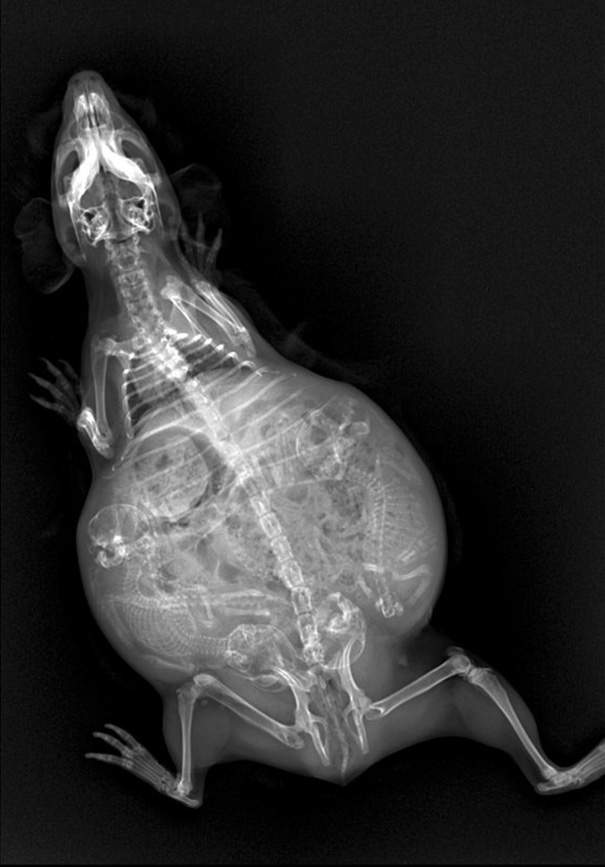

▼懷孕的天竺鼠

圖片來自:boredpanda